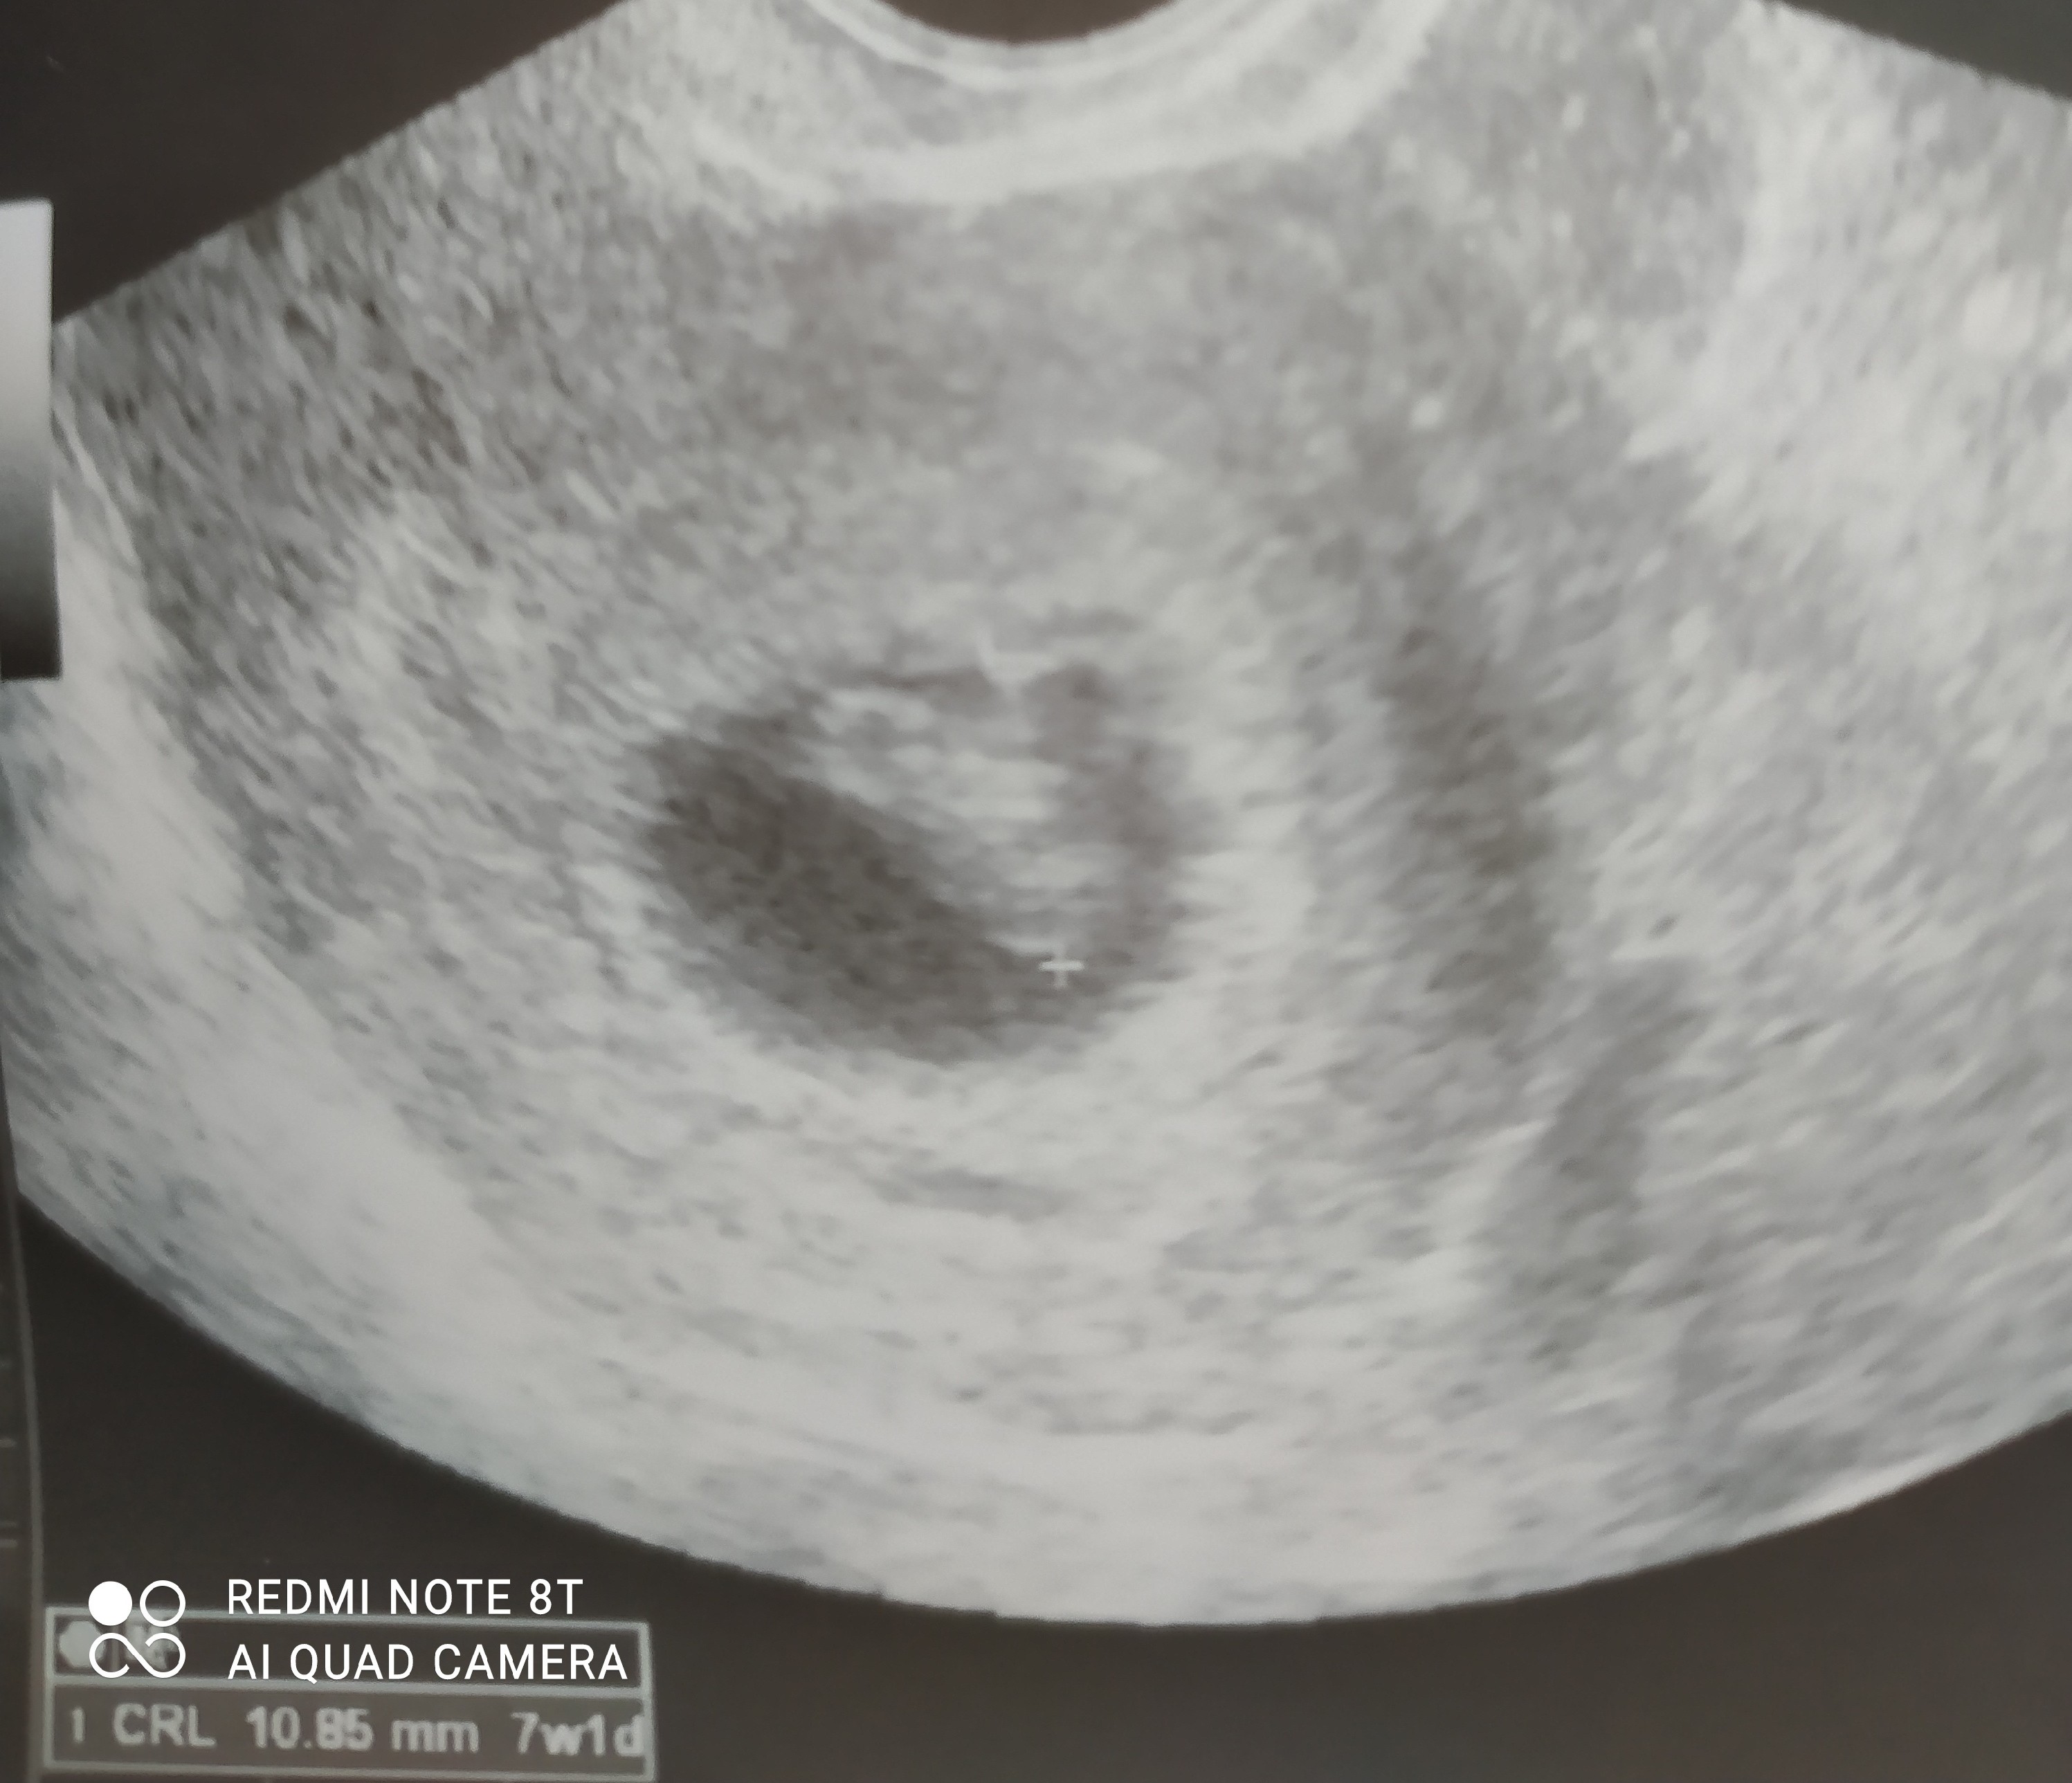

Dziewczyny jest dzidziol i serduszko❤😍oczywiście sie pobeczałam😂😍mężuś też widział😊dostałam luteine dopochwową na te plamienie. Dziś wszystko czyste. Lekarz powiedział , że mogą być one spowodowane neoparinem , acardem i naczynka mogą pękać po wysiłku . Powiedział , że krwiaków nie ma . Mam ciąże wysokiego ryzyka mam się oszczędzać i leżeć. W poniedziałek komplet badań mam do zrobienia. Wstawiam zdjęcie ale kiepskie bo z nfz . We wtorek będę miała lepsze. Cieszę się 😍

• IMG_20210326_172658.jpg

IMG_20210326_172658.jpg

780,4 KB · Wyświetleń: 97